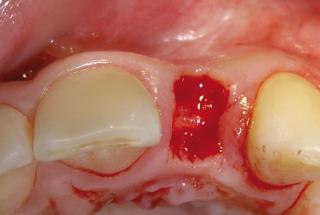

Clinical cases

MPI closely monitors clinical cases in the market to ensure their correct functioning and successful outcome.